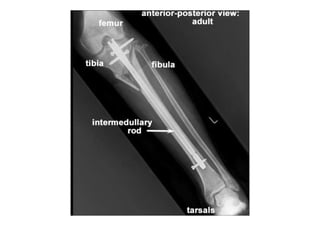

RADIOLOGIA DO

TRAUMA DO ESQUELETO

Referência: http://www.accessexcellence.org/RC/VL/